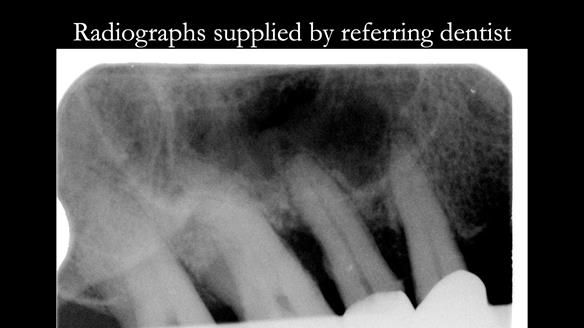

- Bruxism: The upper and lower teeth are worn and chipped due to heavy clenching and grinding. With a powerful bite and limited space for replacement teeth, dental implants supported fixed teeth are not recommended. A simpler solution is a metal-based partial denture/splint (“Combat denture”) as planned below. This will act as a splint to protect and replace the missing teeth.

- Restored Teeth: The remaining upper teeth and lower back teeth have large fillings and crowns, making them structurally weak. The new denture will reduce the forces on these teeth to help them last longer, though they may still require new restorations or extractions occasionally.